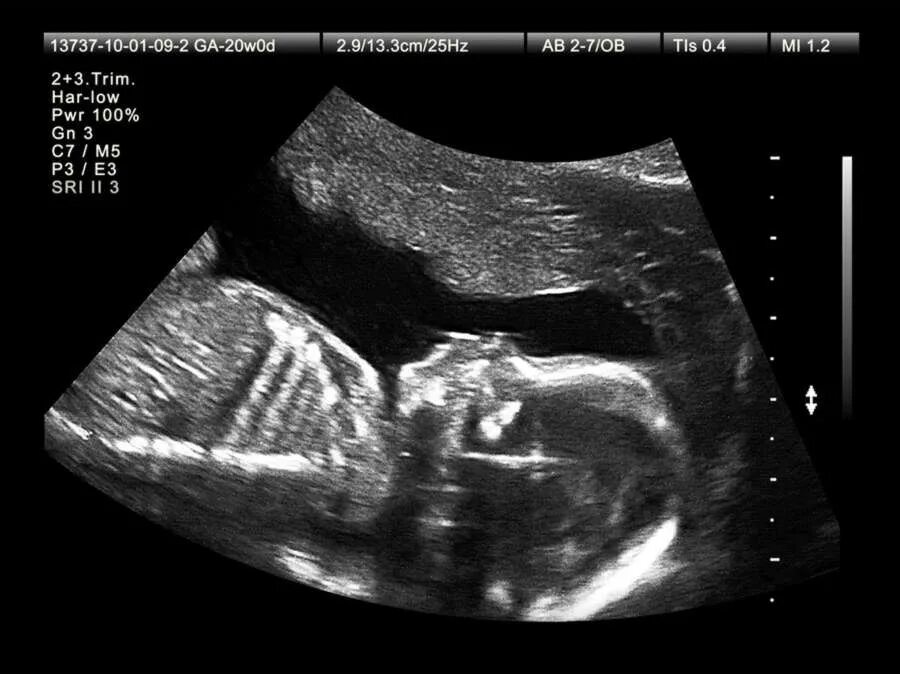

Скрининг два